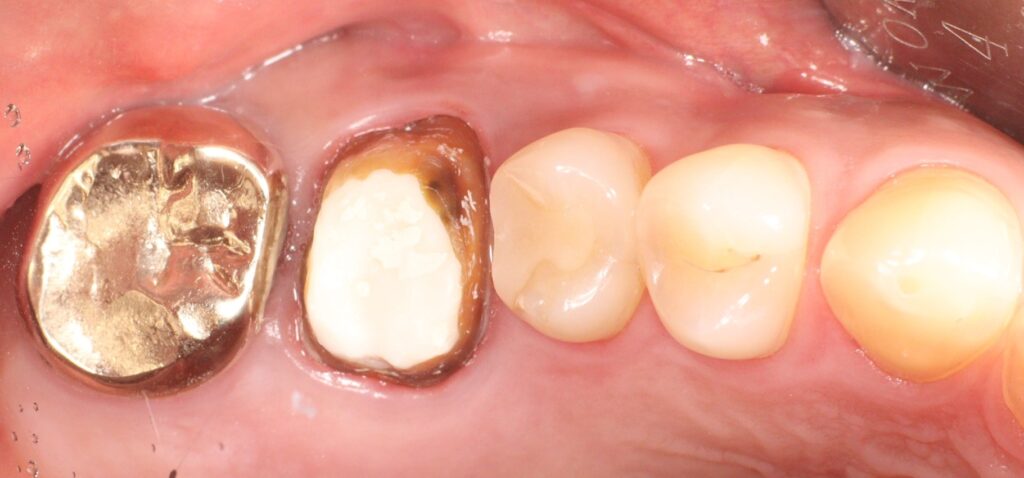

역시 남은 치질이 많이 없었는데요.

치아의 테두리는 남아 있어

재신경치료를 진행하였고

염증과 고름주머니, 통증이 사라져

단단한 재료로 메워 크라운을 진행하도록

준비하였습니다.